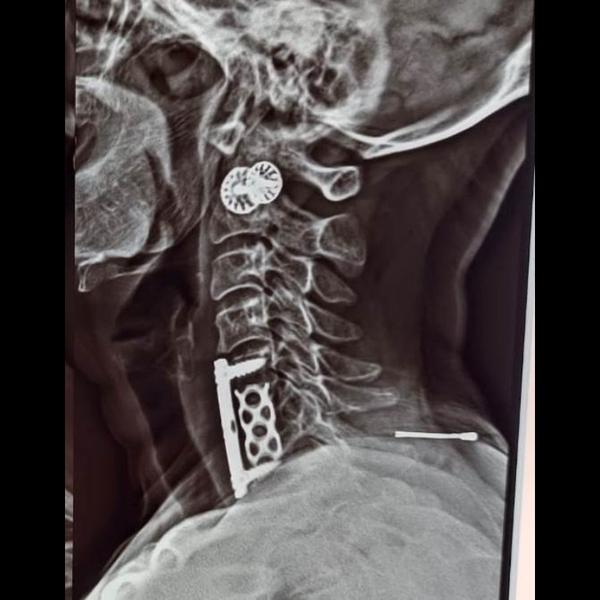

ANTERIOR CERVICAL SPINE FIXATION WITH DECOMPRESSION DISCECTOMY WITH INTERBODY CAGE WITH PLATTING - ...

Anterior cervical discectomy and fusion (ACDF) sur...

ACDF SURGERY IN CASE OF CERVICAL SPINE INFECTION